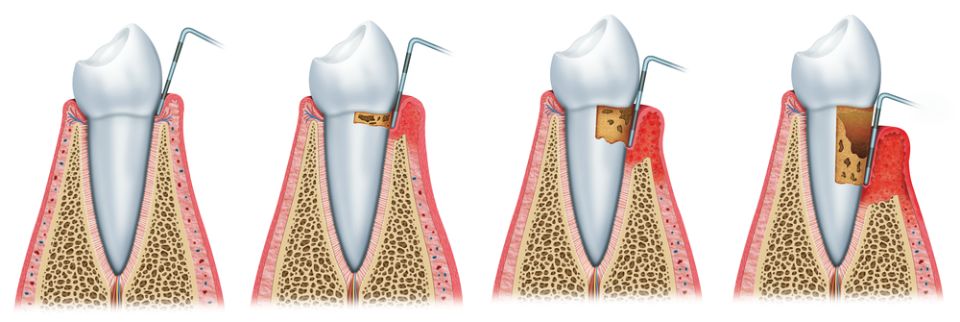

La Periodòncia és lespecialitat odontològica dedicada a lestudi del periodont o lestructura de suport de les dents. Engloba la prevenció, el diagnòstic i el tractament de les malalties que afecten aquests teixits que envolten i subjecten la dent a l'os (geniva, ciment radicular, lligament periodontal i os alveolar).

Dins de les malalties periodontals més conegudes trobem:

La gingivitis que cursa amb inflamació i envermelliment de les genives i possible sagnat al raspallat.

La periodontitis clínicament presenta els signes de la gingivitis però també s'acompanya de la pèrdua dels teixits que suporten la dent: el lligament periodontal i l'os alveolar, causant-ne la mobilitat de la dent i futura pèrdua si no es tracta.

Les causes de la periodontitis són la combinació de la presència de bacteris patògens juntament amb els factors genètics (resistència de cada persona a les infeccions). A part, se li sumen altres factors que poden condicionar la seva evolució com: tabaquisme, hàbits higiènics, certs medicaments, la diabetis...

La recessió gingival no és una malaltia pròpiament dita sinó un trastorn morfològic on el retrocés de la geniva marginal pot presentar problemes estètics i molèsties a causa de la sensibilitat produïda per l'exposició dels colls dentals. Les causes més freqüents són per un raspallat incorrecte, per una sobrecàrrega funcional o bé degut a una periodontitis crònica no tractada.

El nostre objectiu principal és la prevenció de l'aparició de la periodontitis i en cas de diagnosticar-se, tractar-la per poder eliminar la inflamació i poder aturar-ne la progressió. Per això, és important que el pacient tingui un bon hàbit d'higiene bucal i assisteixi a les revisions i visites periòdiques del dentista.

De vegades no podem tractar la periodontitis només amb tractament conservador i cal recórrer a tècniques quirúrgiques per aconseguir millors resultats, per exemple amb la cirurgia periodontal.